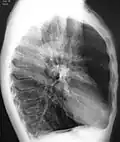

A chest X-ray is not useful to establish a diagnosis of COPD, but it is of use in either excluding other conditions or including comorbidities such as pulmonary fibrosis and bronchiectasis. Characteristic signs of COPD on X-ray include hyperinflation (shown by a flattened diaphragm and an increased retrosternal air space) and lung hyperlucency.[5] A saber-sheath trachea may also be shown that is indicative of COPD.[111]

A CT scan is not routinely used except for the exclusion of bronchiectasis.[5] Pulse oximetry measurement of peripheral oxygen saturation is recommended in people with clinical signs of respiratory failure or right heart failure.[5] An analysis of arterial blood is recommended in those with a peripheral oxygen saturation of 92% or less to determine actual blood oxygen level and assess for high levels of carbon dioxide in the blood, which may have therapeutic implications such as need for non-invasive ventilation or oxygen supplementation.[10] WHO recommends that all those diagnosed with COPD be screened for alpha-1 antitrypsin deficiency.[40]

Chest X-ray demonstrating severe COPD, displaying small heart size in comparison to the lungs

A lateral chest X-ray of a person with emphysema, displaying barrel chest and flat diaphragm

A severe case of bullous emphysema -

Axial CT image of the lung of a person with end-stage bullous emphysema -

Very severe emphysema with lung cancer on the left (CT scan)